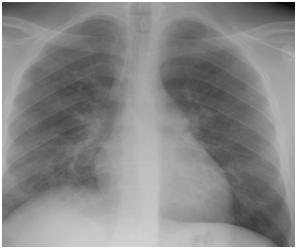

Figure 4A Chest X-ray film on day two from suffering attack of low grade fever.

Figure 4B Follow up Chest X-ray at time of diagnosing H1N1 pneumonia 6 days later.

Figure 4C Follow up Chest X-ray three days after starting oseltamivir therapy.

Figure 4D Follow up chest X-ray after 7 days from starting H1N1 therapy.

Figure 4E Follow up Chest x-ray showing further improvement.

Figure 4F Follow up chest X-ray 4 days after the end of H1N1 therapy.

Figure 4 H1N1 radiological pictures in a diabetic 28-year-old transplant recipient.